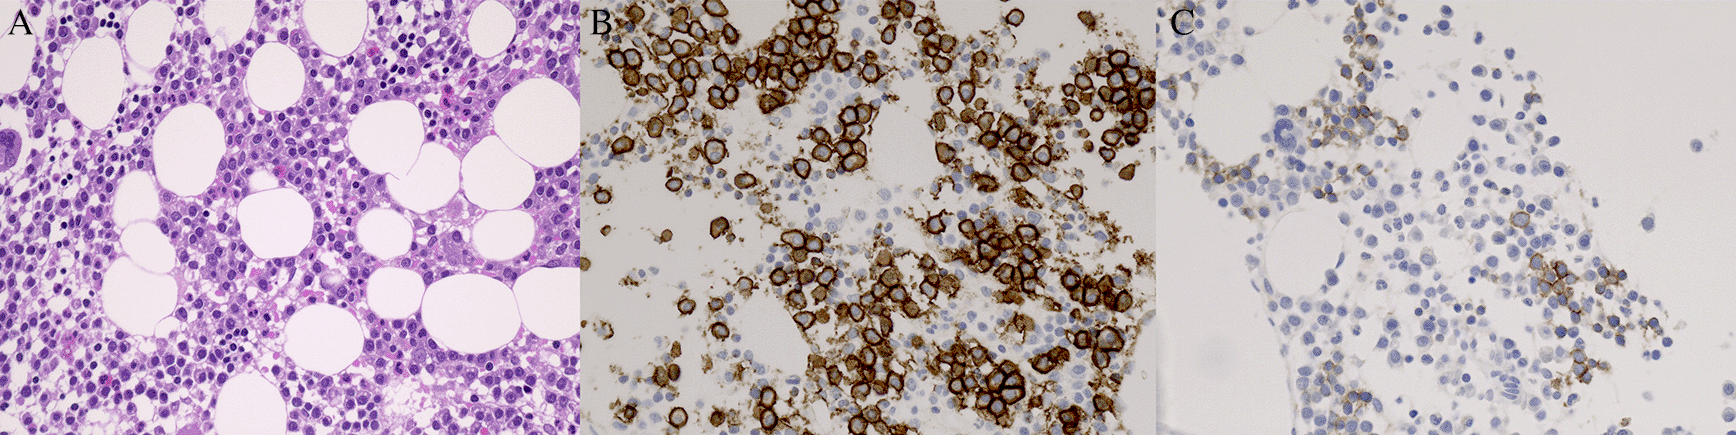

Immunohistochemistry for E- and N-cadherin was performed on BM and EMD biopsy specimen in 31 patients. Tissue sections were cut from formalin-fixed, paraffin-embedded blocks containing MM cells and were processed for immunohistochemistry using an automated staining system (BOND-III, Leica Microsystems, Wetzlar, Germany). For assessment of E- and N-cadherin and CD138 expressions, the E-cadherin rabbit monoclonal antibody (Cell Signaling Technology Cat# 3195, RRID:AB_2291471), N-cadherin mouse monoclonal antibody (Abcam Cat# ab98952, RRID:AB_10696943) and CD138 mouse monoclonal antibody (Agilent Cat# M7228, RRID:AB_2254116) were applied at 1:600, 1:4,000 and 1:50 dilutions, respectively, followed by detection using the BOND Polymer Refine Detection kit (Leica Biosystems Cat# DS9800, RRID:AB_2891238). Antigen retrieval was performed with BOND Epitope Retrieval Solution 2 (EDTA, pH=9.0). Positive staining of MM cells was independently evaluated by two pathologists, K.M. and S.H., without any clinical information (Cohen’s κ score 1.0). At a magnification of 200, one field with the highest cadherin positive myeloma cell count on each slide was selected. The percentage of E- or N-cadherin-positive MM cells was calculated using the equation E- or N-cadherin-positive MM cells/total BM nucleated cells, regardless of the number of hematopoietic cells. A score >0.5% was used to determine positivity (yes vs. no) (Figure 1). The percentage of BM plasma cells was calculated using the equation CD138-positive cells/total BM nucleated cells, regardless of the number of hematopoietic cells.

(A) BM biopsy with MM cell infiltrate. Hematoxylin and eosin stain. Consecutive sections of BM biopsies were stained with antibodies against (B) CD138 and (C) E-cadherin. Note that E-cadherin was clearly stained in the membrane of MM cells. MM, multiple myeloma; BM, bone marrow.

Figure 1 shows typical E-cadherin positivity by immunohistochemistry in a patient with MM. Table 115 depicts the results of E-cadherin expression in conjunction with various clinical parameters at diagnosis. E-cadherin expression was positive in 25 (80.6%) of the initial 31 BM samples. At initial screening, EMD was found in 14 (45.2%) cases. Four additional patients developed EMD on follow-up from 17 patients who had no EMD at diagnosis. Negative E-cadherin expression at diagnosis (found in six patients) was significantly associated with the presence of EMD (p=0.0041). At diagnosis, all 14 (100%) of the patients with EMD had osseous lesions; none (0%) had extraosseous lesions (Table 2). No association was found between N-cadherin expression and the presence of EMD.